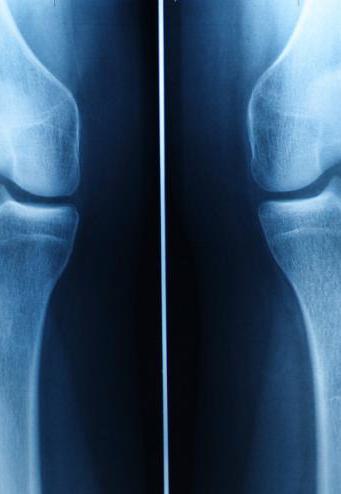

Challenges in Cartilage Regrowth

Cartilage’s complex structure requires more than just cell injection for effective regeneration. Scaffold-like structures are being researched for better outcomes.